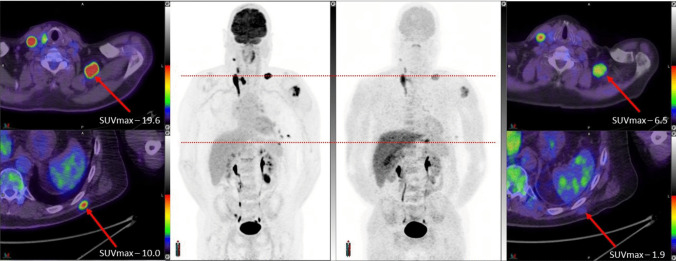

Results: Across the trial cohort, no adverse safety signals resulted from [18F]MEL050 administration. The whole-body effective dose was 0.0163 mSV/MBq for an adult male and 0.0206 mSV/MBq for an adult female. The human biodistribution was favorable with low uptake in organs at high risk of metastatic spread, including the brain. Of metastatic sites identified as melanoma on [18F]FDG PET/CT, only 31/65 (48%) were positive on [18F]MEL050 PET. Four [18F]FDG+[18F]MEL050+ metastases were resected from three patients and found to be melanotic by histological examination, whereas five [18F]FDG+[18F]MEL050- metastases from two patients were amelanotic. In our historical cohorts, amelanosis was more common in metastatic than primary disease (45% versus 20%) and the presence of melanin within sentinel lymph node metastases was associated with worse disease-free (HR 2.3 95% CI 1.3 - 4.3, p = 0.002) and disease-specific survivals (HR 3.6, 95% CI 1.4 - 9.7,p = 0.009) in stage III disease, compared with amelanotic sentinel lymph node metastases.